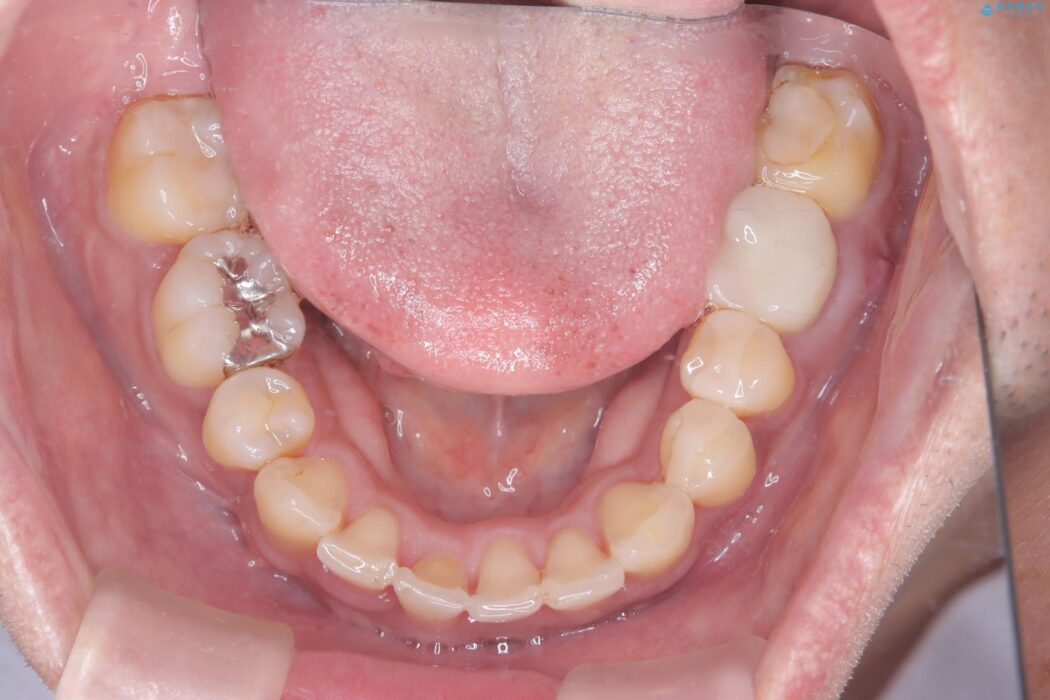

噛み合わせのズレが右側で大きかった(2級)ため、右側上下2本の歯を抜歯し、ワイヤー矯正で噛み合わせを左右対称の理想的な位置に改善しました。

気になっていた八重歯や凸凹が改善され、大変ご満足いただけました。